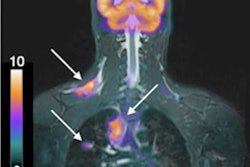

PET/MRI is better than MRI alone for the detection and staging of nodes and distant metastases in women with breast cancer, according to a study presented by German researchers at the recent RSNA 2019 meeting.

Researchers from the University of Düsseldorf in Germany found that the combination of PET with MRI was statistically superior to MRI alone for normal detection and staging, as well as in the detection of distant metastases (M staging).

A total of 298 lesions were included in the study. As for the nodal analysis, PET/MRI correctly detected nodes in more patients (83%) than MRI (74%), as well as more patients with positive nodes. PET/MRI also detected 87% of all nodes, compared with 75% for MRI alone. All of the aforementioned results were statistically significant in favor of PET/MRI.

The researchers also noted distant metastases in seven patients (6%). PET/MRI identified all seven subjects (100%) and detected all of their metastases (100%). Unfortunately, both PET/MRI and MRI alone also had false-positive findings in four patients. Relative to the lesion-based analysis, PET/MRI detected all 31 metastatic lesions (100%). MRI detected only 18 (58%) of those metastases, resulting in a statistically significant difference in favor of PET/MRI.